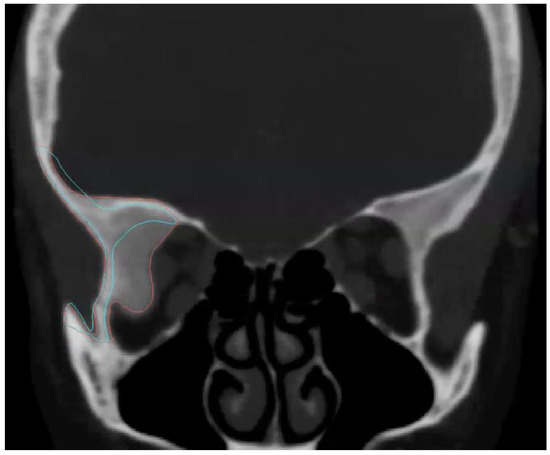

2.2. Preoperative Study and Virtual Surgical Planning

4.2. Surgery Virtual Planning: CAD CAM Technology